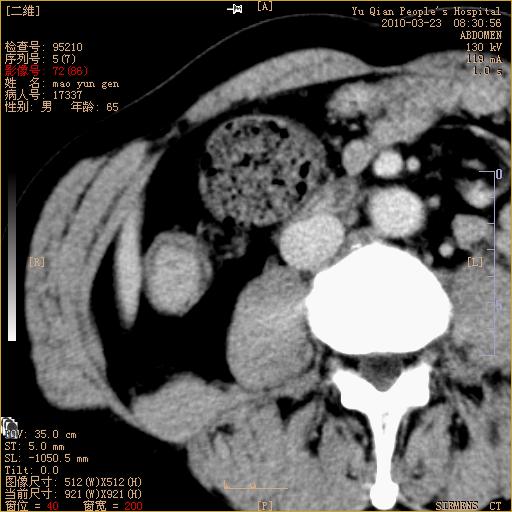

标题: CT25266:消瘦月余,前来肝部检查,请看看肠腔 [打印本页]

标题: CT25266:消瘦月余,前来肝部检查,请看看肠腔

升结肠肠壁增厚,不均强化,考虑升结肠腺癌可能性,建议肠镜检查。

1)考虑升结肠癌。2)右肾小囊肿。